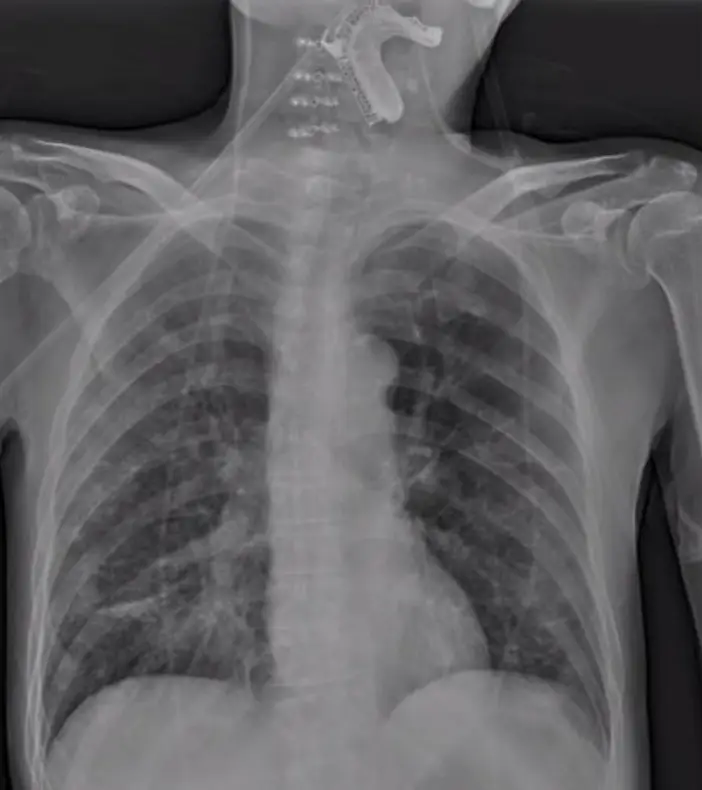

病人曾接受頸椎手術及腦瘤手術,腦瘤術後因水腦放置 V-P shunt,因吞嚥困難放置鼻胃管,此次因新冠病毒感染住院,住院時的胸部 X 光如圖(六),經治療後病況改善,1 週後病人突然血氧下降、痰液變多及意識變差,同時發現有解血便,當日胸部 X 光如圖 (七)。下列何項檢查處置,應最優先被執行?

– 初次胸部X光(圖六)可見雙肺野清晰無明顯浸潤,並見一條電磁密度適中的管路沿食道下行至胃部,位置符合胃管放置路徑。

– 一週後胸部X光(圖七)顯示頸部及上縱膈區域出現一條電磁密度較高的管狀構造,其走形與典型食道路徑不符,且位於氣管前方,提示管尖已誤置入氣道或咽喉部(pmc.ncbi.nlm.nih.gov)。此時患者突然血氧下降、痰量增加、意識改變並有解血便(melena),合併影像異常走形高度懷疑NGT誤置。